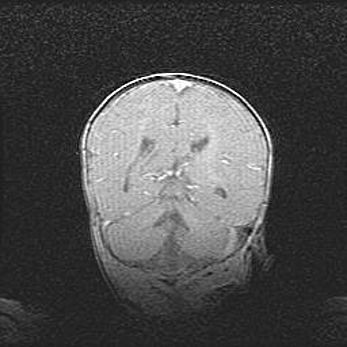

Наружная гидроцефалия с возможной атрофией височных областей.

Возраст: 28 дней

Вес: 3670 г

Пол: мужской

Окружность головы: 38 см

Срок гестации: 40 недель

Гидроцефалия головного мозга у новорожденных – это заболевание, которое характеризуется скоплением избыточного количества спинномозговой жидкости в желудочковой системе головного мозга в результате затруднения её перемещения от места выработки к месту поглощения в кровеносную систему или вследствие нарушения абсорбции. При открытой наружной форме гидроцефалии у новорожденных расширяются и переполняются субарахноидные пространства.

При нормотензивных  формах,  которые,  как  правило,  являются  следствием  перенесенных ишемических  повреждений  паренхимы  мозга,  возможно  сочетание микроцефалии  с нормотензивной гидроцефалией. В основе данных изменений лежит атрофия больших полушарий с преимущественной  локализацией  в  лобно-височных  областях.